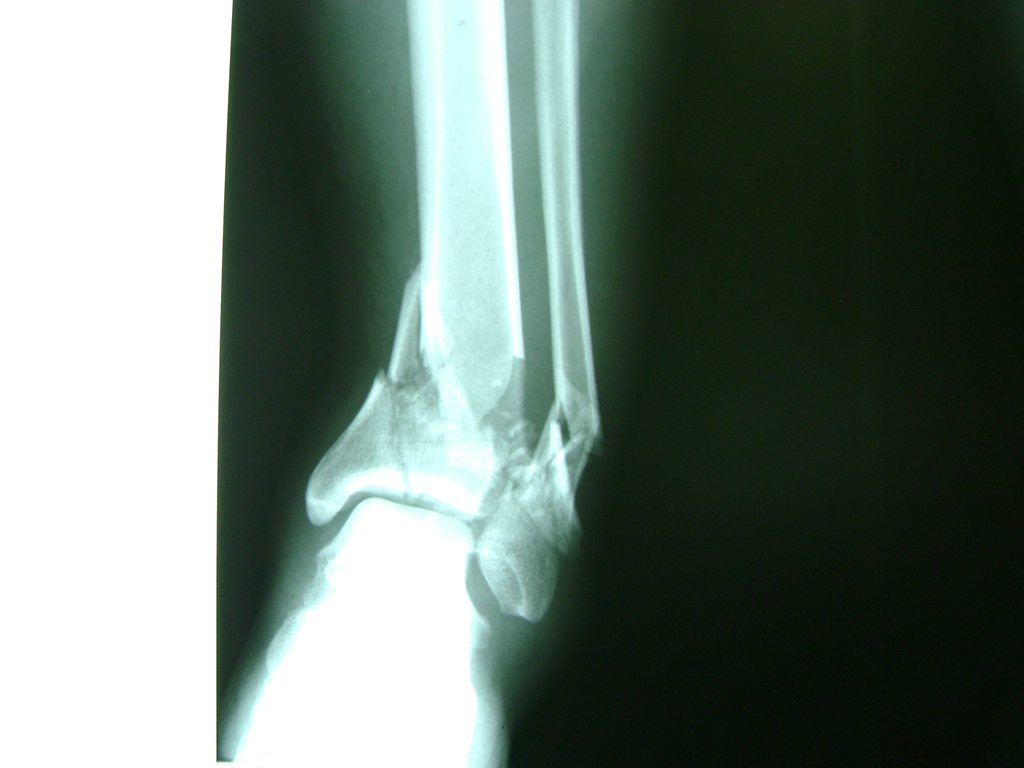

Calcaneo - Tobillos

Una fractura de tobillo es la rotura de uno o más de los huesos del tobillo. Estas fracturas pueden ser:

Algunas fracturas de tobillo pueden requerir cirugía si:

- Los extremos de los huesos están desalineados entre sí (desplazados).

- La fractura se extiende hasta la articulación del tobillo (fractura intra-articular).

Cuando se necesita cirugía, es probable que esta implique el uso de clavijas de metal, tornillos o placas para sostener los huesos en su lugar mientras la fractura se consolida. Los elementos de soporte pueden ser temporales o permanentes.